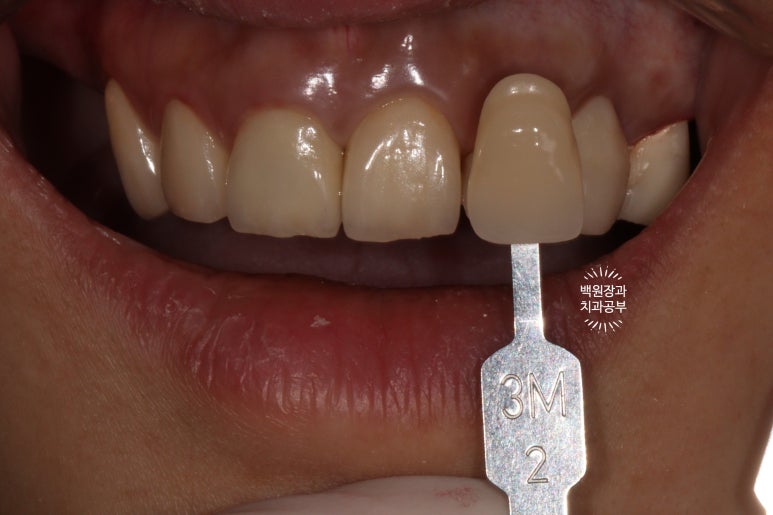

원하시는 치아 색상을 파악하기 위해, VITA shade guide 를 가지고 환자분과 함께 색상을 정해봅니다.

보통 앞니는 조금 더 밝은색을 선호하시는 듯 해요.